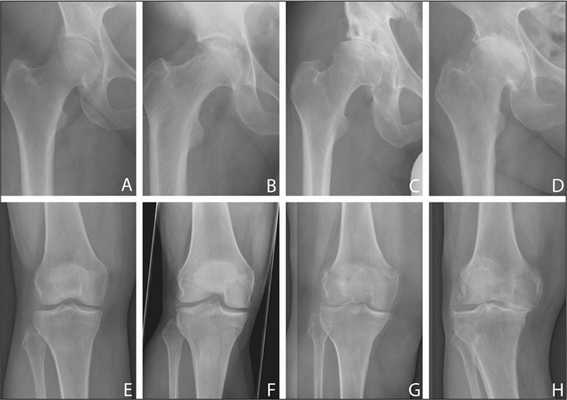

Артроз коленного сустава на рентгене.

Показания к замене

Посмотрите на рентген, на нем вы видите, до какой степени при запущенном гонартрозе изношен гиалиновый хрящ, обеспечивающий гладкое скольжение суставных поверхностей. Концевые участки костей грубо деформируются нарушая функции сгибания и разгибания конечности вызывая интенсивный болевой синдром.

Динамика болезни на рентгене.